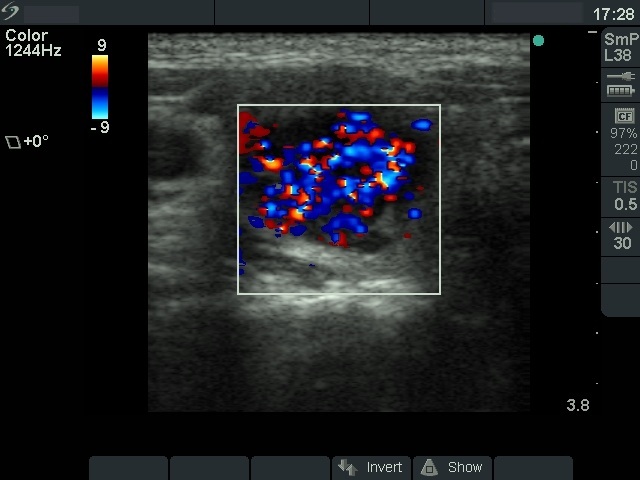

Ultrasonography: a solitary cystic nodule in the right lobe with increased "blood flow".

Six mL brown cystic fluid was aspirated. Cytological report: benign, cystic degeneration.